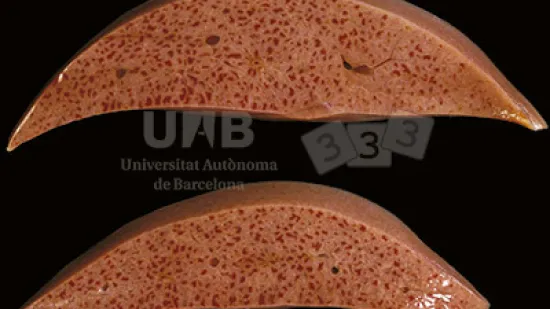

Semaine du 26-Avr-2021

Quelle lésion peut être observée sur ce rein ?